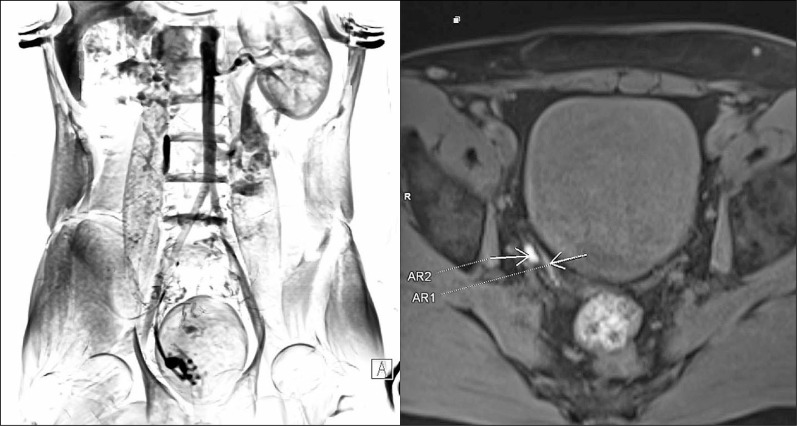

无精子症在10-15%的男性中被诊断为不孕症。梗阻性无精子症发生率为20-40%,其特征是卵泡刺激素值正常,睾丸大小正常,附睾增大。梗阻性无精子症是男性不育的常见原因。几种成像技术用于评估精液通畅,包括:阴囊超声、经直肠超声(TRUS)和阴囊磁共振成像(MRI),其中血管造影被认为是金标准。然而,每种方法都有其局限性,没有一种单一的测试可以提供全面的诊断。本文介绍了一种将高分辨率多平面MRI与经典血管造影的精道通畅功能评估相结合的尝试。精管阻塞程度的详细描述可能有助于决定是否需要手术治疗。

Azoospermia is recognised in 10-15% of men diagnosed due to infertility. Obstructive azoospermia occurs in 20-40% in this group of patients and it is characterised by normal FSH values, testes of normal size, and epididymal enlargement. Obstructive azoospermia is a common cause of male infertility. Several imaging techniques are used to assess the patency of the seminal tract, including the following: scrotal ultrasound, transrectal ultrasound (TRUS), and scrotal magnetic resonance imaging (MRI), with vasography being considered a gold standard. However, each of these methods has its limitations, and no single test can provide a comprehensive diagnosis. This article describes an attempt to combine high-resolution multiplanar MRI with functional evaluation of the patency of the seminal tract of classical vasography. A detailed description of the level of spermatic duct obstruction may help decide whether the condition qualifies for surgical treatment.